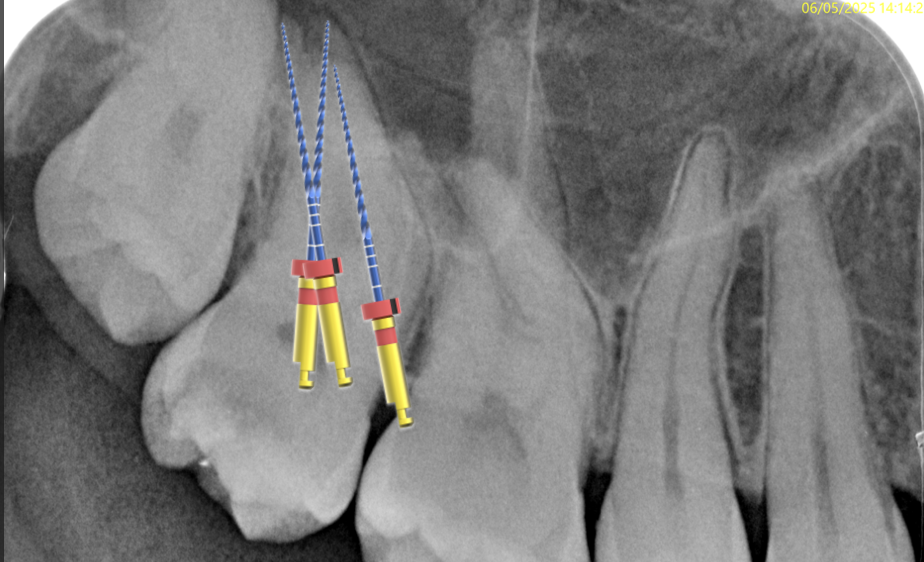

Fig. 5

I started with pre flaring the root canals by using the RR file (17/.10) in the coronal third